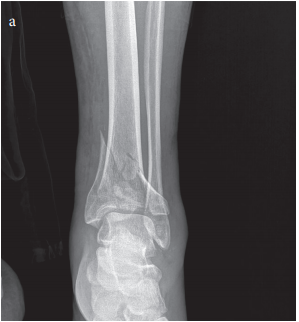

Pilon fractures, involving the distal tibia near the ankle, continue to challenge the field of orthopaedic trauma with their tricky parts and tangled issues. Managing these injuries requires a careful balance between achieving proper bone alignment and preserving the soft tissue envelope – a task many clinicians find both intimidating and nerve-racking. In this opinion editorial, we take a closer look at Minimally Invasive Plate Osteosynthesis (MIPO) as an alternative to the conventional open reduction and internal fixation (ORIF) for treating pilon fractures, offering insights into its functional and radiological outcomes, as well as the benefits and limitations of its use.

The distal tibia’s anatomy is packed with small details that make pilon fractures one of the most complicated pieces in trauma care. Pilon fractures stem largely from high-energy trauma – such as falls from height or motor vehicle accidents – and come with considerable soft tissue damage. The treating team must sort out several tangled issues:

The standard ORIF approach offers the advantage of direct visualization of the fracture and the possibility of achieving precise reduction. However, it often involves extensive surgical dissection. This makes the procedure off-putting when it comes to preserving the blood supply and further complicating the soft tissue situation. Given these nerve-racking restrictions of traditional treatment, clinicians are increasingly exploring less invasive options.